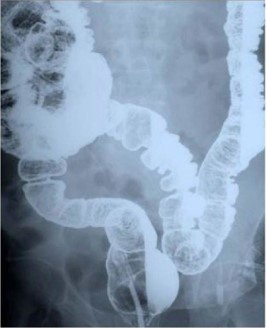

Figure 3: Acute colonic pseudo-obstruction (X-ray).

Haustra and gasin the colon.

When the redundant sigmoid colon becomes symptomatic, the differential diagnosis is ‘acute colonic pseudo-obstruction’ which is associated with ‘intestinal neural dysplasia’ [9]. The erect plain abdominal x-ray appears different from that of a sigmoid volvulus (Figures 2 & 3).